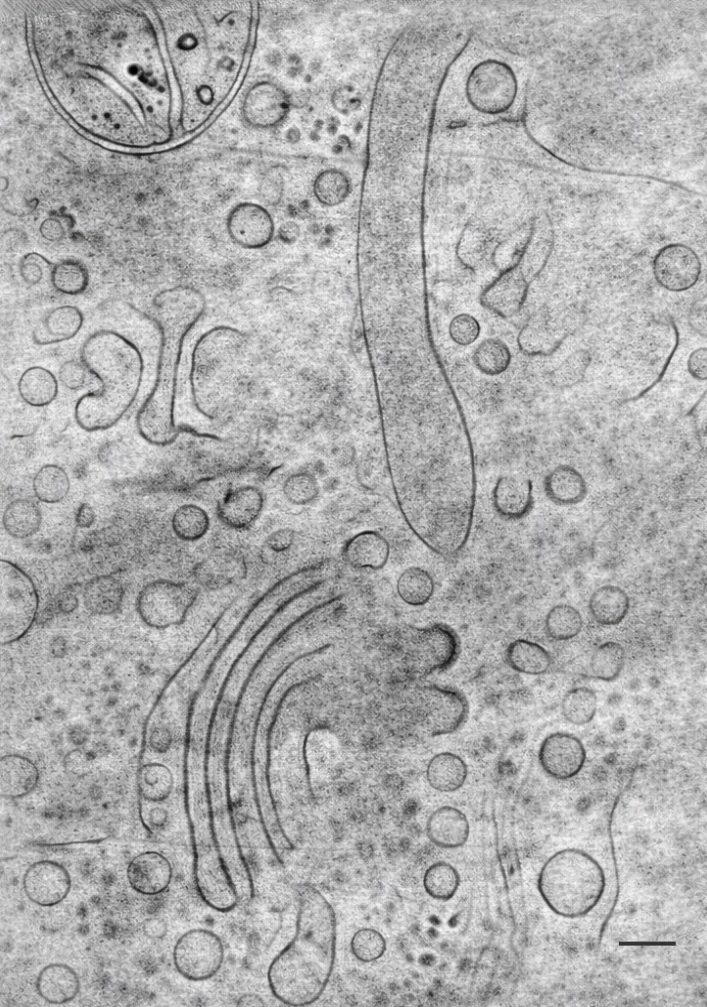

According to Prof. Segal-Peretz, “Using the new instrumentation, Technion researchers will be able to observe a wide range of phenomena at molecular resolution while preserving the natural environment of the molecules by rapidly freezing them to temperatures of minus 170°C. This will make it possible, for example, to see how a drug binds to its target protein to perform its therapeutic function, or how a human cell transports molecules through the nuclear envelope to initiate the expression of specific genes. Another example is deciphering the mechanism by which polymers self-organize to impart desired properties for various engineering applications.”

Photo credit: Rami Shlush